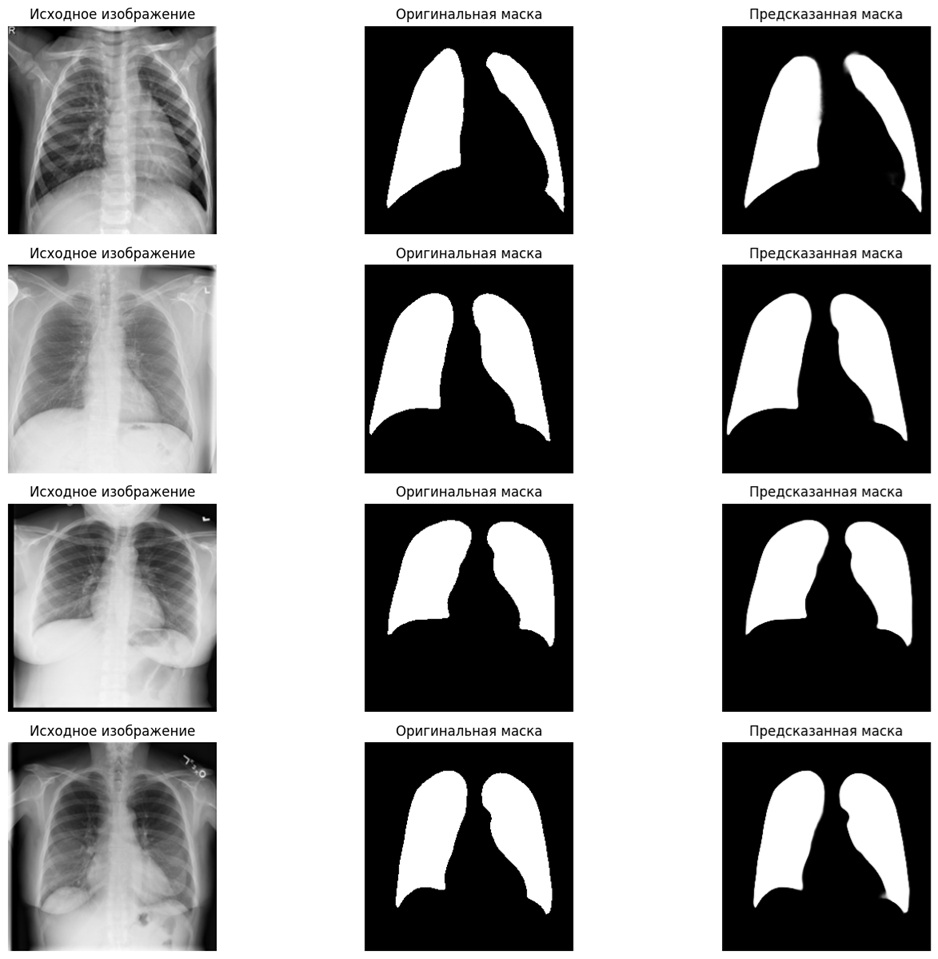

📊Визуализированы результаты, позволяющие сравнить оригинальные снимки, маски и предсказания модели

✅Система стабильно распознаёт границы лёгких даже на сложных снимках

✅Достигается высокая точность сегментации, близкая к экспертной разметке

✅Возможна наглядная проверка качества работы через визуализацию результатов